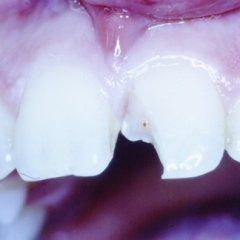

P3: Il trattamento endodontico si rende necessario quando la polpa del dente, comunemente chiamata dai Pazienti “nervo” è stata irrimediabilmente danneggiata da carie penetranti, fratture dentali, traumi o da cause imputabili a pratiche odontoiatriche scorrette. A volte la devitalizzazione del dente si rende necessaria, in corso di riabilitazioni protesiche complesse, per prevenire possibili problemi di ipersensibilità o per poter coinvolgere nel progetto terapeutico di recupero denti già di per se compromessi dal punto di vista parodontale. Presupposto per ottenere il successo in tale terapia è l’applicazione di un serio protocollo operativo che prevede tra l’altro l’uso di un telo di lattice, chiamato comunemente “diga”, che consenta la detersione e la pulizia dei canali del dente in un ambiente sterile e il controllo delle diverse fasi del trattamento attraverso delle radiografie endorali.